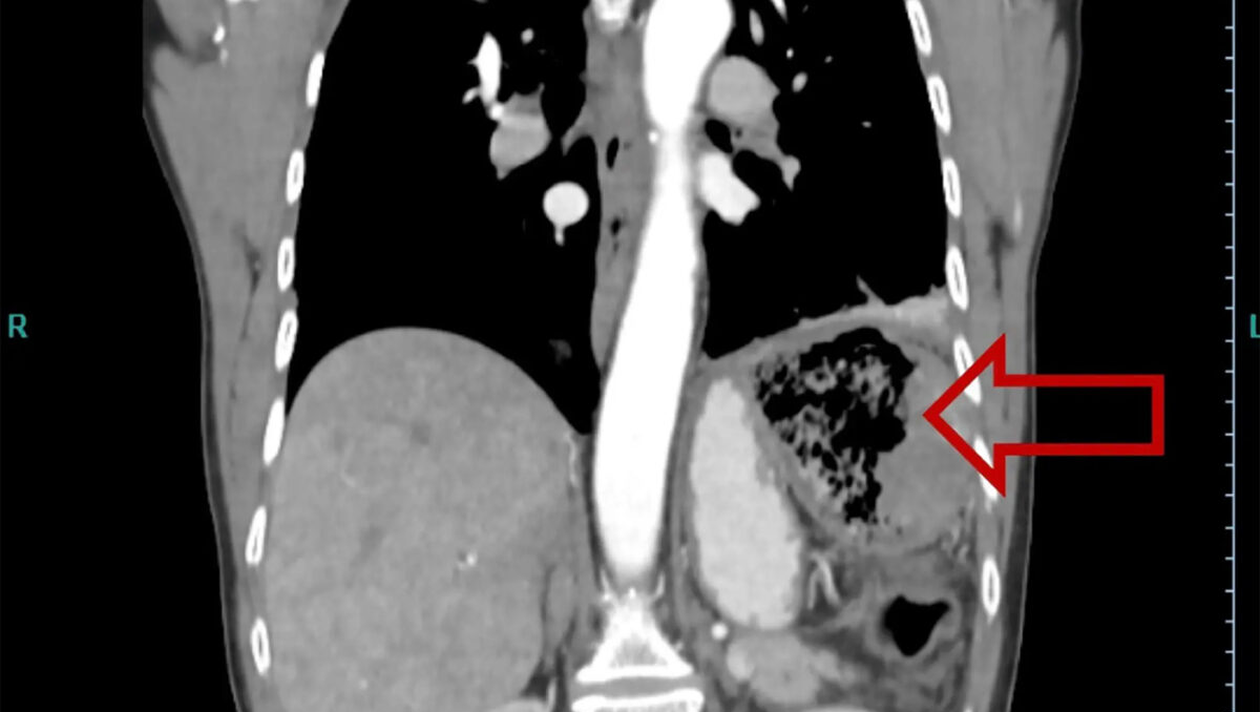

După ce s-a vindecat de cancer, la 20 de ani de la momentul intervenției chirurgicale, a început să aibă dureri abdominale severe, febră, transpira pe timpul nopții. S-a confruntat cu anorexie și slăbise excesiv. Femeia, fiind alarmată de aceste lucruri, a mers la spital. A făcut și o radiografie în urma căreia s-a descoperit că avea în partea stângă a intestinului un obiect. Era, de fapt, bucata de cârpă lăsată de medicul care a operat-o în anul 1999.

A intrat în operație, iar medicii i-au îndepărtat obiectul rămas în intestin. Nu este prima oară când se întâmplă astfel de greșeli medicale, arată nypost.com.